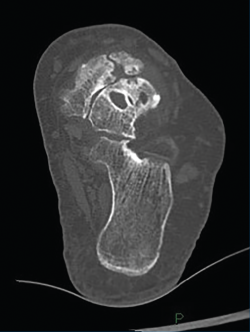

Figura 5. En este corte de tomografía de la región talonavicular se aprecia la existencia de cartílago no dañado en la región medial de la articulación y la afectación en la región más lateral, lo que conforma la artrosis asimétrica típica de la enfermedad de Müller-Weiss.

La utilización de plantillas con una cuña pronadora/valguizante y soporte del arco longitudinal interno permite la mejoría clínica al forzar el desplazamiento de la cabeza del astrágalo hacia la región medial del navicular que mantiene un cartílago “no utilizado” en buen estado(10)(Figuras 5 y 6). Cuando el tratamiento conservador no es suficiente para aliviar el dolor y la limitación funcional del paciente, las cirugías artrodesantes de la región medial del pie parecían ser la técnica de elección(11,12,13). El restablecimiento del arco medial del pie con una artrodesis talonavicular, una triple tarsiana o una talonaviculocuneiforme parecía ser el tratamiento de elección en la cirugía para la EMW(14,15,16,17). El problema era la dificultad para corregir el varo del retropié desde un abordaje medial y las dificultades existentes para conseguir una consolidación con un hueso navicular que no presentaba gran cantidad de hueso subcondral esponjoso y sangrante. Además, las fuerzas deformantes de la articulación en una EMW son lateralizadoras/varizantes, lo que explica el elevado porcentaje de ausencias de consolidación. De hecho, algunos autores utilizan para la artrodesis un implante a modo de banda de tensión estática lateral en la articulación talonavicular que trata de contrarrestar las fuerzas de traslación lateral del navicular en la EMW(18).